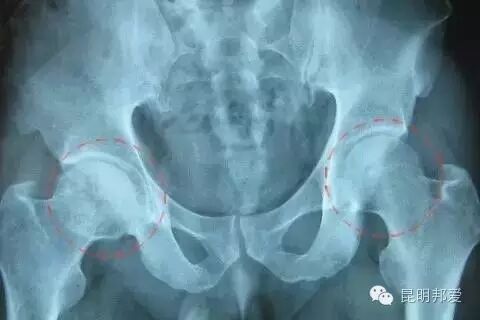

4、X线表现

骨纹理细小或中断,股骨头囊肿、硬化、扁平或塌陷。二、股骨头坏死原因